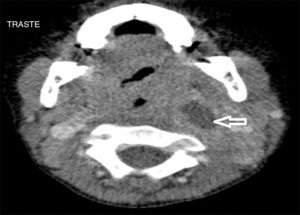

Se han recuperado estudios de imagen de 63 pacientes, a los que se les realizaron 71 pruebas. Las técnicas utilizadas han sido 36 TAC (50,7%), 20 ecografías (28,2%), 8 radiografía lateral de cuello (11,3%) y 7 RMN (9,9%). Al 62,5% (5 de los 8) de los que se realizó radiografía lateral de cuello y al 15% (3 de los 20) de los pacientes a los que se les realizó ecografía, hubo que completarles el estudio con TAC o RMN. A los pacientes a los que se les realizó TAC o RMN no hubo que hacerles más pruebas de imagen. La TAC ha sido empleada fundamentalmente en ACPI de localización más profunda (ARF, APA y APF), mientras que la ecografía fue empleada en ACPI más superficiales (AA y AS) (figs. 1 y 2).

Las técnicas de imagen más utilizadas han sido la TAC y la ecografía, empleadas en un 86% de los casos. Se usó cada una en diferente situación: la TAC preferentemente en abscesos de localización profunda y la ecografía en abscesos superficiales. La TAC se ha usado en el 100% de los APF y en el 75% de los ARF. La ecografía se usó en el 78% de los AS y en el 70% de las AA, siendo, no obstante, la prueba inicial en muchos casos con objeto de evitar radiaciones innecesarias a niños de corta edad14. Aunque la TAC supone una prueba que requiere colaboración del paciente (puede precisar sedación) e implica radiación del niño, en nuestra opinión es la prueba de elección ante ACPI de localización profunda, si hay mala respuesta al tratamiento o ante la sospecha de complicaciones y es, además, la herramienta más útil para la planificación de la cirugía3–5. La radiografía lateral de cuello, bastante utilizada en los servicios de urgencias, se ha usado solo en 8 ocasiones, todas en ARF, y en nuestro caso con una clara tendencia a la disminución en su uso. Por otro lado, en los últimos años estamos empleando más la RMN tanto como herramienta diagnóstica como para control radiológico ante la sospecha de persistencia de un ACPI tras la cirugía, evitando así radiaciones a los niños.